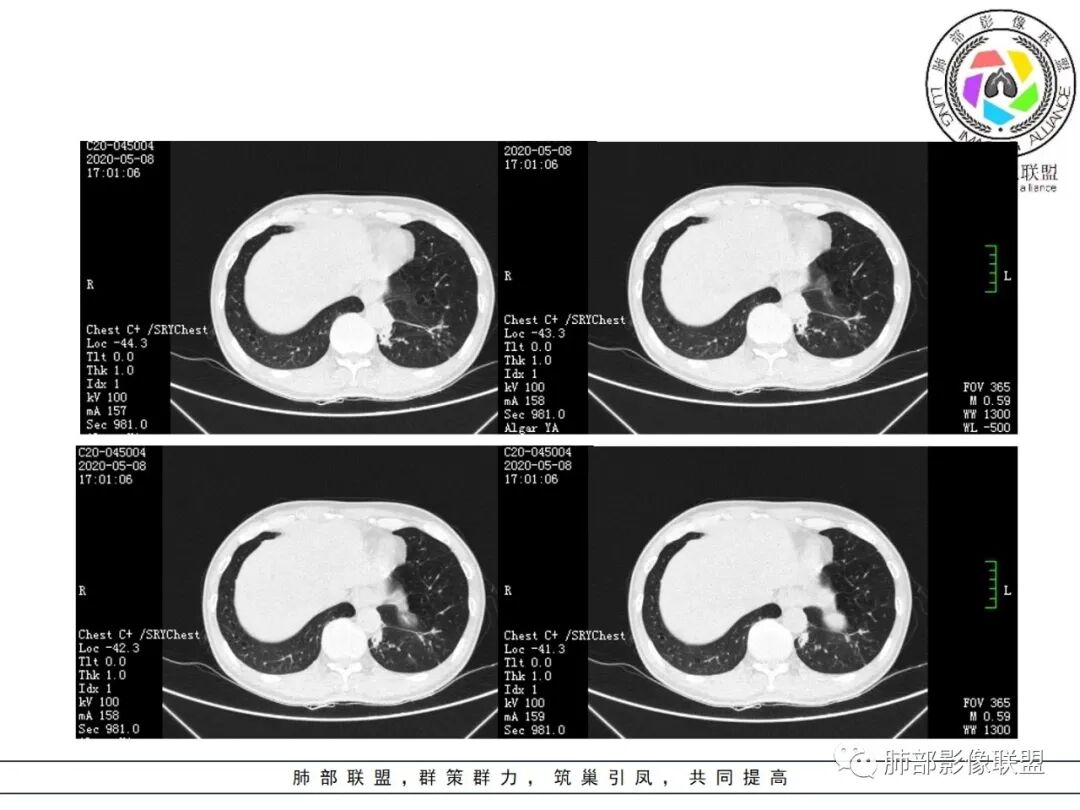

临床资料:老年男性,咳嗽咳痰2月余,慢性病史。有吸烟史40年(现已戒烟),抗感染治疗2周肺部病灶未见吸收。

影像所见:

肺气肿背景。

结节伴分叶。

斑片影,考虑阻塞性炎症。

支气管壁厚,支气管腔内高密度影填充。

周围散在斑片影及结节影,类似“小花花草草”的感觉。